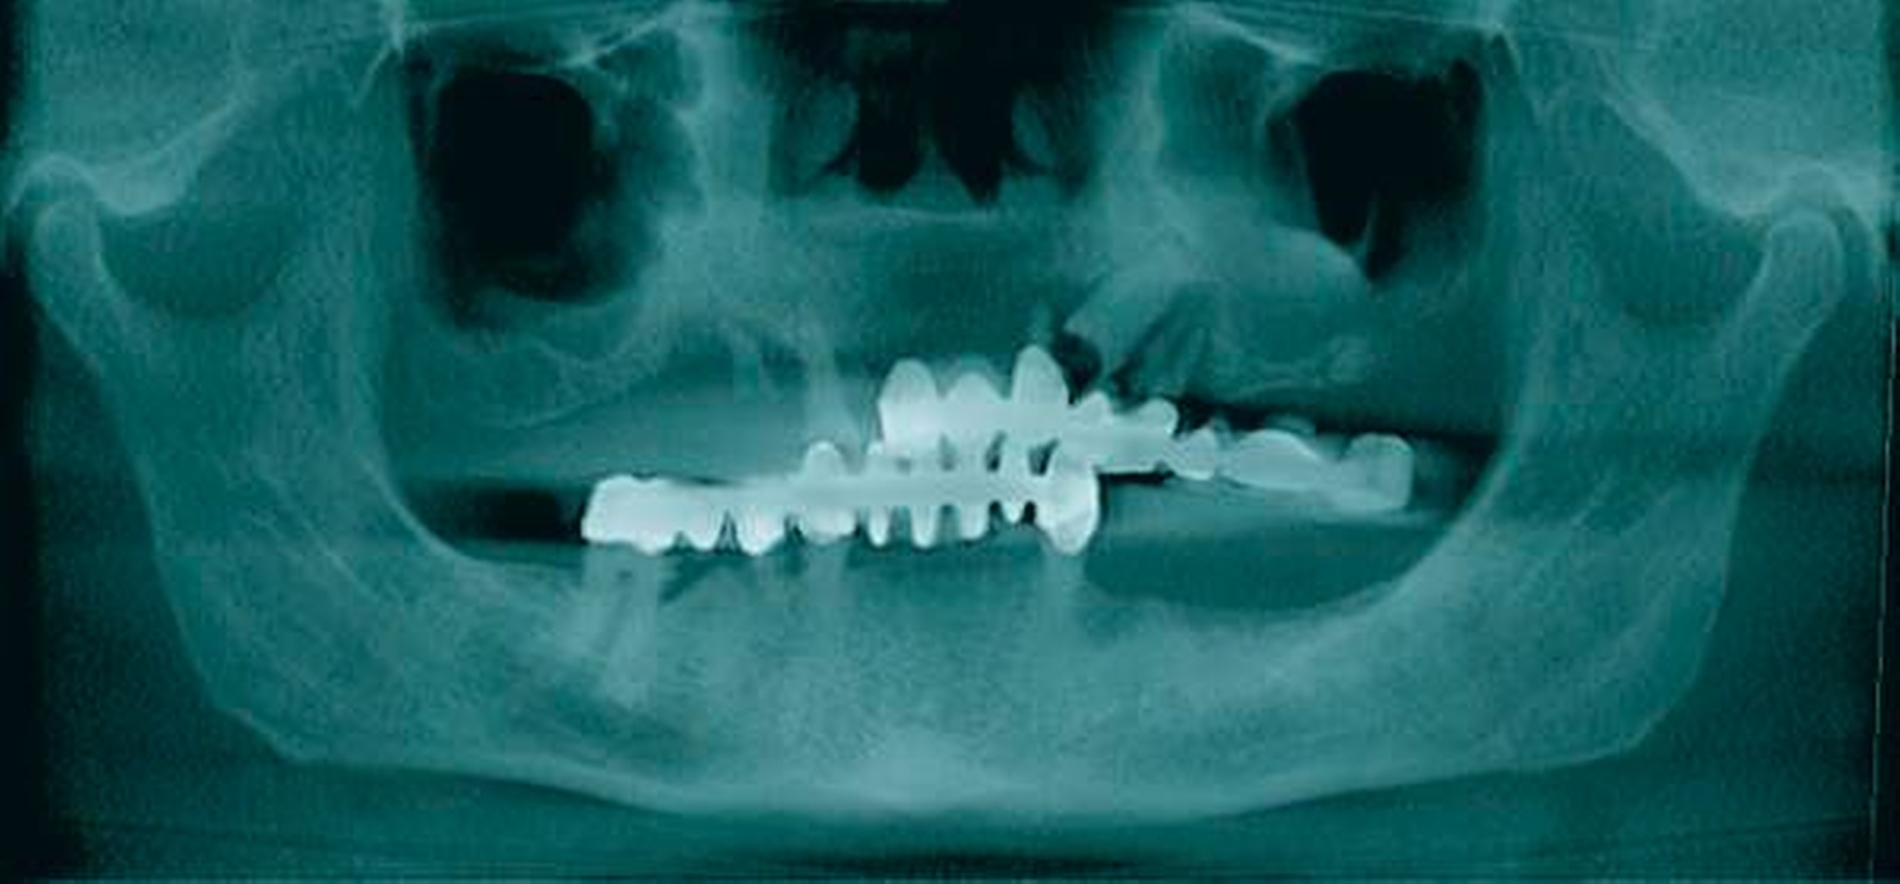

In der durchgeführten radiologischen Diagnostik zeigten sich ausgeprägte Parodontopathien mit Verdacht auf eine BRONJ bei gut begrenzter radiologischer Aufhellung mit Kieferhöhlenbeteilung (Abbildungen 3 bis 5). Unter der Verdachtsdiagnose einer BRONJ wurde somit die Indikation zur Zahnsanierung mit Exzision der pathologischen Veränderung im Oberkiefer gestellt. Nach Entfernung der gelockerten Brücke zusammen mit den die Brücke tragenden Zähnen zeigten sich große Mengen harten, anhaftenden Gewebes (Abbildung 6); der unter dem Befund liegende Knochen stellte sich klinisch als vital und ohne Anzeichen einer Nekrose dar.